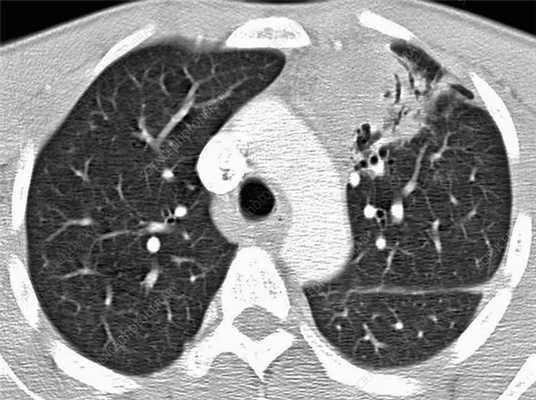

Первично диссеминированные заболевания легких выявляются по результатам аппаратных медицинских обследований (КТ, рентген). На посрезовой компьютерной томографии легких (МСКТ) в высоком разрешении очаги диссеминации и фиброза визуализируются лучше всего. Врач-рентгенолог может оценить объем поврежденной легочной ткани, выявить фиброзные тяжи (соединительнотканные спайки и рубцы), скопление жидкости и(или) гноя в альвеолярных пузырьках, сопутствующие патологии дыхательных путей, артерий, лимфатической системы.

Диссеминация представляет собой множественные патологические очаги (уплотнения) диаметром 1-10 мм. На КТ-сканах они выглядят как светлые пятна, в то время как в норме легочная ткань визуализируется практически однородным темным цветом. Очаги могут быть абсолютно разными по размеру, форме (эллипсообразные, с неровными краями) и морфологии. Нередко вокруг очагов обнаруживается перифокальное воспаление. Они могут сливаться и в таком случае напоминают инфильтративные процессы при пневмонии. Диссеминация также проявляется в виде очаговых микро повреждений с кровью и отеками.

Гранулематозы и диффузно расположенные «матовые стекла» на КТ не являются специфическим признаком туберкулеза. Первые обнаруживаются и при саркоидозе, а вторые — при пневмониях и других заболеваниях.

Пневмокониоз тоже носит гранулематозный характер. На КТ-сканах отчетливо видны множественные узелковые уплотнения разной плотности. Такие уплотнения следует проверять на предмет того, является ли процесс доброкачественным, нет ли онкологической угрозы.

Саркоидоз легких - это онкологическое заболевание. Его основными признаками на КТ являются диссеминация и медиастинальная лимфаденопатия. Диссеминация на сканах выражена не так ярко как при прогрессирующем туберкулезе, однако определенное сходство есть. Диагностику затрудняет легочный фиброз. Вместе с дессиминированнным поражением дыхательного органа присутствуют васкулиты, периваскулиты, перибронхит.

Лимфома легких на КТ

Признаки лимфомы легких особенно выражены на четвертой стадии заболевания, когда болезнь поражает дыхательный орган. На КТ при этом будут видны увеличенные лимфоузлы, формирующие цепочки, конгломераты. При этом у пациента может также наблюдаться отек легких. Однако высокая разрешающая способность КТ позволяет выявить лимфому на ранней, первой стадии.

На КТ лимфомы, как и любые уплотнения, визуализируются сравнительно более светлым цветом. В норме воздушная легочная паренхима практически однородного темного цвета. Иногда таких уплотнений несколько и они диссеминированны. Контуры лимфомы четкие и ровные. Вокруг патологических очагов обнаруживаются участки «матового стекла».